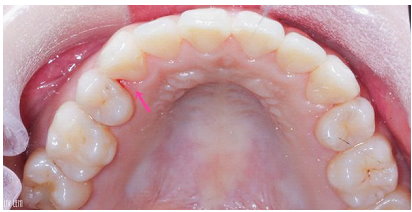

你們看~這是我牙周治療前的口腔狀況,

在診所的診療用強光下才發現我有幾顆牙的牙齦邊緣,

已 經 出 現 牙 結 石 了!

牙肉也稍微的紅腫,這程度真是我察覺不到的!!!!

(什麼!!?

竟然還有流血!!!)

所以牙周病被稱隱形殺手根本沒有誇張!

治療前的上排內側。

治療後的上排內側,沒有紅腫流血囉~~~~

除了牙結石消失不見,上排牙齦消腫服貼不少!